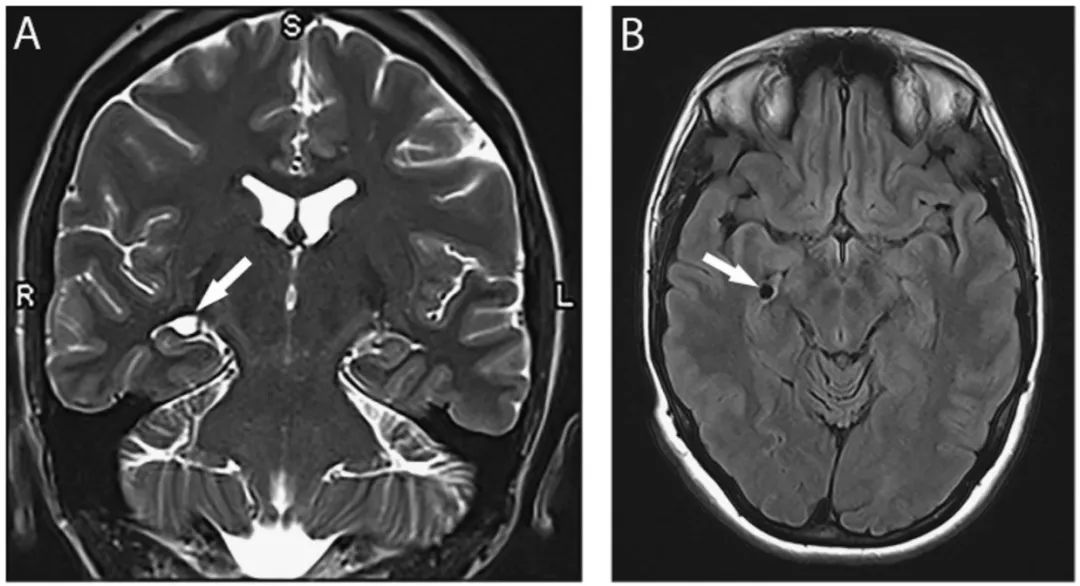

图3 脉络膜裂神经上皮囊肿

(A) 冠状位T2WI显示位于海马区上方,起源于脉络膜裂的囊肿(箭头);(B)FLAIR像显示同一囊肿(箭头)位于中脑外侧、颞叶内侧。